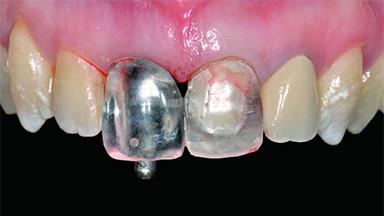

A 30-year-old patient presented at our clinic with a chief complaint of pain in her endodontically treated right maxillary central incisor (tooth 11) with a post-and-core and a fixed single crown. She had a very high lip line, a medium to thin soft-tissue phenotype, and a medium scalloped gingival contour. She also had high esthetic expectations because of her young age and beautiful smile. However, her expectations were realistic and she understood the risks of the treatment. At the initial clinical examination there was a slight mobility of tooth 11; no fistula was observed. The patient also had a single crown on the adjacent tooth 21. Both restorations were old and esthetically deficient. A digital periapical radiograph showed a very small periapical radiolucency, a thick intraradicular post, and no separation between root fragments.